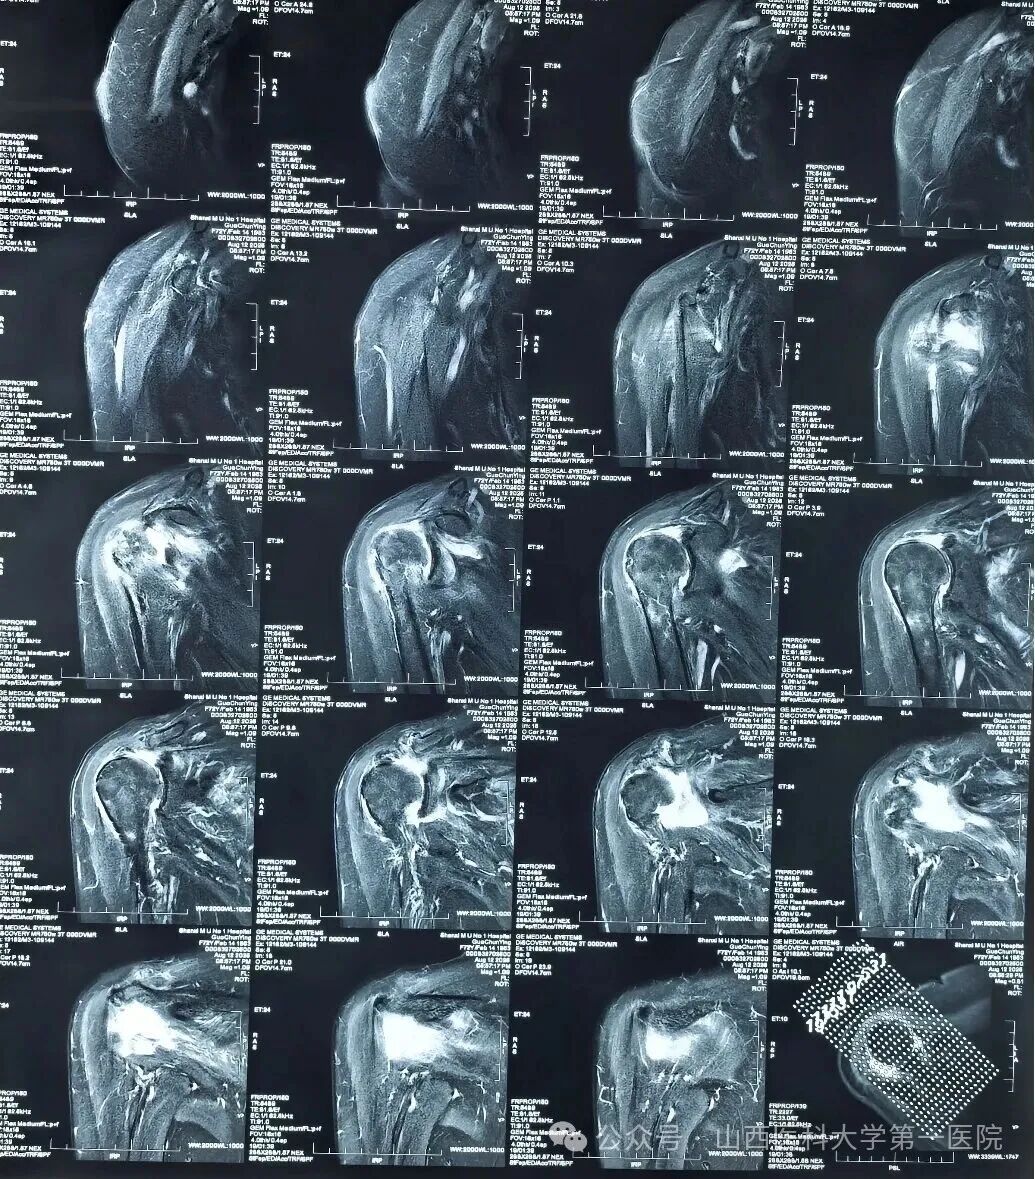

术前右肩MRI显示巨大间隙撕裂

72岁的郭女士在无明显诱因的情况下出现肩关节活动范围逐渐受限,半月前就诊当地医院并完善右肩MRI提示右肩巨大肩袖撕裂。针对郭女士的病情结合查体,杨自权团队诊断为“不可修复的右侧巨大肩袖撕裂”,在详细向患者及家属说明病情并介绍治疗方案后,郭女士及其家属选择行“微创可吸收球囊植入术”进行治疗。